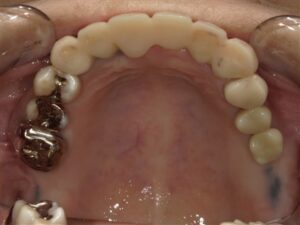

before

after

左上56インプラント

今回のインプラント手術は左上の第二小臼歯、および左上第一大臼歯部分に行なっております。

上顎の第一大臼歯相当部分の上方には上顎骨内に上顎洞と言われる空洞が存在していますが、インプラント手術中のドリルで上顎洞との境界を損傷してしまうと術後に上顎洞内に炎症を起こし、術後合併症として上顎洞炎を発症します。

同部の手術において最も重要なことは上顎洞の損傷を引き起こさないことです。

その為に当院では術前に十分にCT画像を読影し歯科技工士と協力してサージカルガイドを用いて0.1ミリ単位でドリル方向を調整しています。